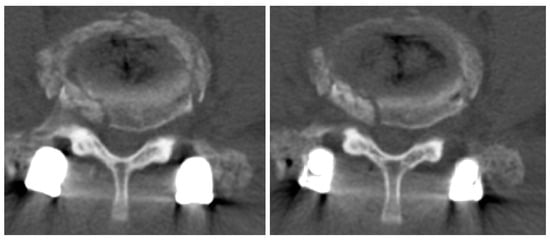

2.2. Case 2